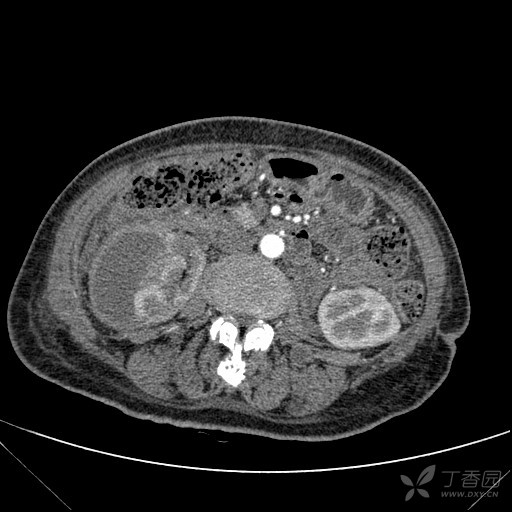

自发性双肾包膜下血肿求原因

自发性双肾包膜下血肿,求原因